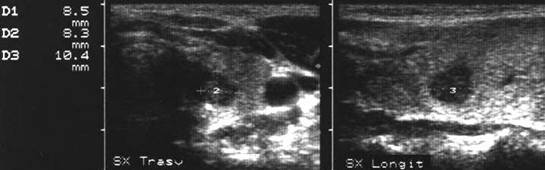

Lob stang, proiectie trasversala si longitudinala

Barbat de 55 ani. Formatiune nodulara voluminoasa ce ocupa 2/3 din lobul stang, hipoecogena, neomogenea, de 20 x 23 x 44mm(10 cc). Citoaspirata ecoghidata: carcinom midolar. Confirmat histologic.